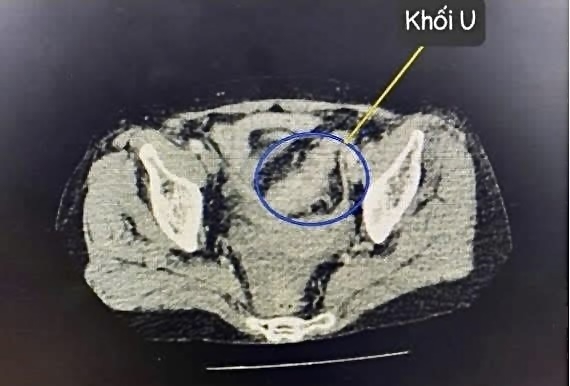

Hình ảnh khối u trên phim chụp

Với bệnh nhân nữ 64 tuổi tại Bệnh viện Đa khoa Ninh Bình: Viêm phúc mạc do khối u đại tràng hoại tử vỡ là một tình trạng nghiêm trọng, xảy ra do một khối u đại tràng bị hoại tử, sau đó vỡ ra làm các chất trong khối u và vi khuẩn tràn vào khoang phúc mạc gây viêm nhiễm. Đây là một biến chứng nguy hiểm, có thể gây các biến chứng nặng nề như: nhiễm trùng huyết, sốc nhiễm trùng, suy đa tạng và có thể tử vong.